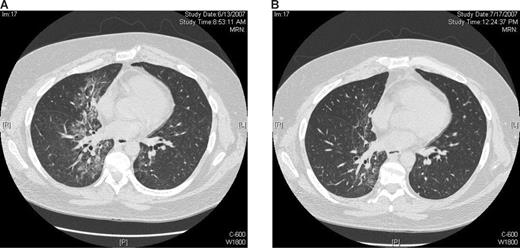

Patient 3520 (white male, age 35, HD, dose level 3.0) had demonstrated clinical and radiologic regression of malignancy followed later by disease progression after his first infusion of 3.0 mg/kg ipilimumab. He was retreated with the same dose of ipilimumab 4 months after his first infusion. He was noted to have new bilateral ground glass opacification in bilateral upper lung fields on a routine reassessment CT scan at 4 weeks after the second infusion. Bronchoscopy revealed no infective etiology except β-hemolytic Streptococcus from a single culture and transbronchial biopsy showed inflammatory changes. The infiltrates worsened despite antimicrobial therapy. He was commenced on methylprednisolone with marked radiologic improvement at 2- and 4-week reassessments (Figure 1). Complete tapering of the patient's corticosteroid therapy over the next month was associated with significant exacerbation of pulmonary infiltrates and dyspnea leading to intubation while radiologic evidence of his HD resolved completely. Repeat transbronchial biopsy showed acute and chronic inflammatory changes only. Reinstitution of corticosteroids accompanied by infliximab (single dose 10 mg/kg) resulted in rapid improvement and eventual complete resolution of dyspnea and pulmonary infiltrates. However, despite a much slower taper, discontinuation of corticosteroid therapy was associated with recurrence of grade 4 pneumonitis. The patient responded completely to treatment with methylprednisone accompanied with a 4-week course of infliximab (10 mg/kg per week) and mycophenylate mofetil. Slow tapering of corticosteroid therapy followed by maintenance therapy with low-dose methylprednisolone and mycophenylate mofetil has prevented subsequent recurrence of the patient's pneumonitis.

Pneumonitis after retreatment with ipilimumab. CT scans of the chest from patient 3520 (dose level 3.0 mg/kg). Scans show (A) an extensive inflammatory infiltrate that developed approximately 6 weeks after retreatment with ipilimumab and (B) complete resolution of changes after corticosteroid therapy.